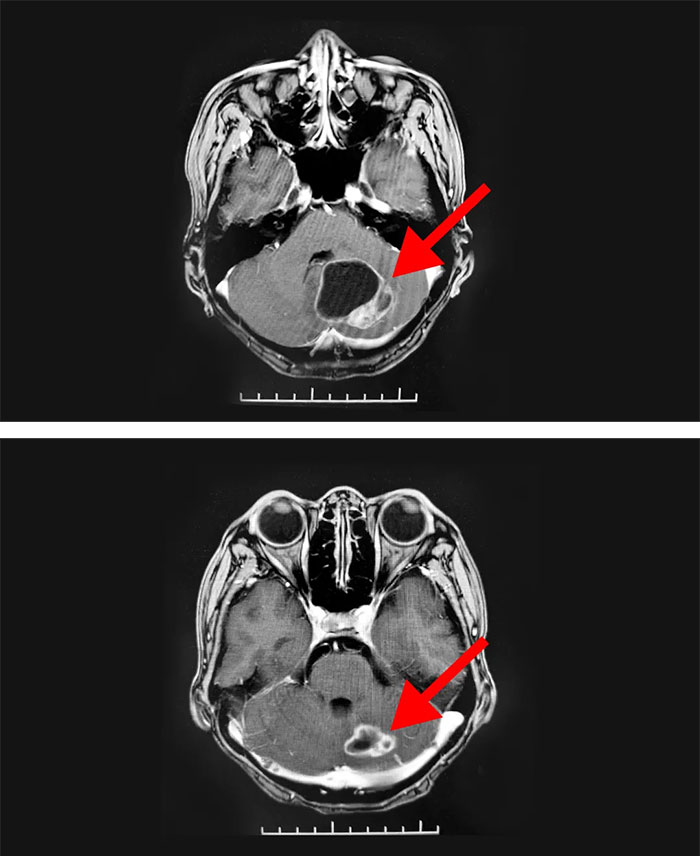

年近六旬的史女士(化名),11年前確診乳腺癌并進(jìn)行了手術(shù)切除。這些年來(lái),她經(jīng)過(guò)多次放、化療治療控制病情,但在2019年11月復(fù)查時(shí),發(fā)現(xiàn)全身多發(fā)骨轉(zhuǎn)移,并立即開(kāi)展治療。今年6月,她突然出現(xiàn)頭暈等癥狀就醫(yī)檢查,經(jīng)外院診斷,明確為左側(cè)小腦半球轉(zhuǎn)移瘤。

隨后,患者慕名來(lái)到上海藍(lán)十字腦科醫(yī)院放療科,通過(guò)放療一個(gè)月后順利出院。近期,患者回院復(fù)診,影像學(xué)檢查顯示,病灶明顯縮小,患者對(duì)治診結(jié)果表示滿(mǎn)意。臨走時(shí),她緊緊握住科室主任王曉東的手表達(dá)由衷感謝:“我是聽(tīng)朋友介紹說(shuō)你們的放療設(shè)備先進(jìn),醫(yī)生團(tuán)隊(duì)專(zhuān)業(yè)?磥(lái)是來(lái)對(duì)了!”

▲ 經(jīng)過(guò)放射治療,病灶明顯縮小